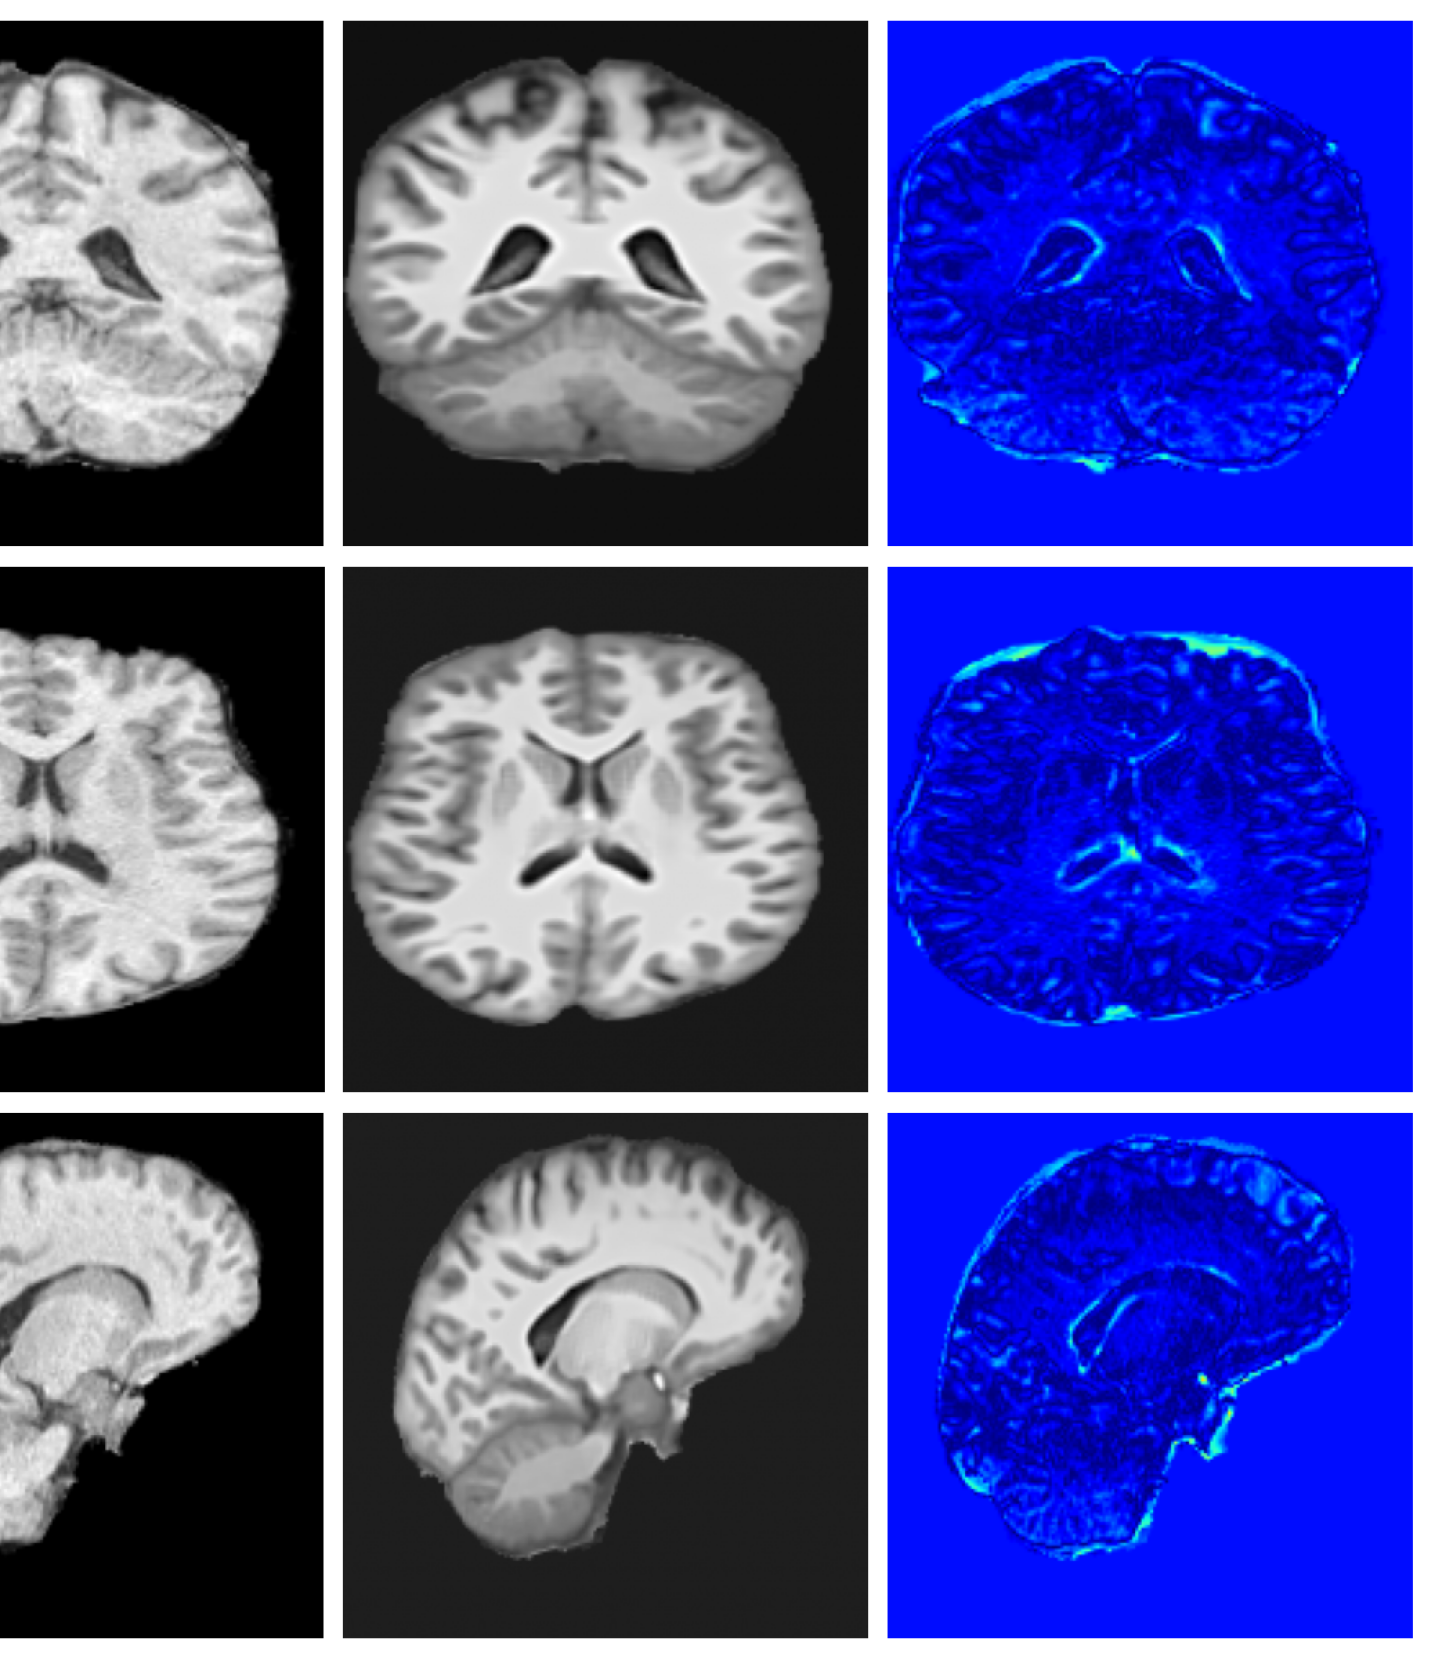

Qualitative T1w results are shown in Figure 2, with further examples for other modalities in Appendix A.8. LoHiResGAN and Res-SRDiff produce unrealistic images with severe artifacts, likely arising from bias fields, sharp intensity artifacts, and other noise not present during training. UniRes generates oversmoothed images, likely due to its TV prior and its reliance on information from multiple input modalities, whereas we apply it unimodally. Di-Fusion shows less pronounced but still notably blurry, voxelated reconstructions which lack the fine-grained details generate by our method. This is likely, in part, due to our use of synthetic rather than real noisy training data, which the method was designed for. As such data is scarce, and in our case unavailable, this requirement represents a significant limitation of Di-Fusion. SynthSR, whilst not as well as our method, does preserve key anatomical structures. However, our difference maps show reduced contrast, further supporting the strong quantitative results shown in Table 2.

Figure 3 (additional examples in Appendix A.9) shows that SynthSR preserves healthy tissue but struggles with large lesions, while DDPM-2D and DDPM-3D, despite producing high-contrast anomaly maps, generate unrealistic homogeneous inpainting, consistent with their lower performance in Table 3. In contrast, our method yields the most anatomically plausible inpainted regions, although anomaly maps appear subtle due to low contrast between lesions and healthy tissue.

A.8 Additional qualitative restoration results

Additional qualitative results for the Clinical dataset are given in Figures 7, 8 and 9, and for the Low-field dataset in Figures 10 and 11.

A.9 Additional qualitative inpainting results

Additional qualitative results for the ATLAS and BraTS datasets are given in Figures 12 and 13, respectively.